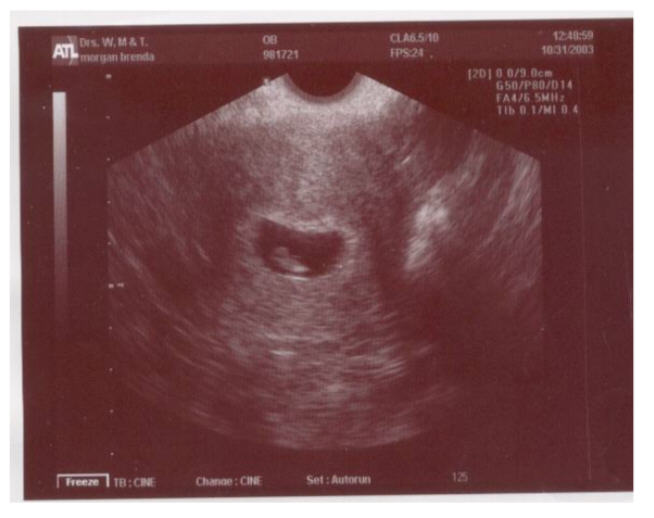

7 weeks |

10/31/2003 |

Doctor Appointment. Had ultrasound. |